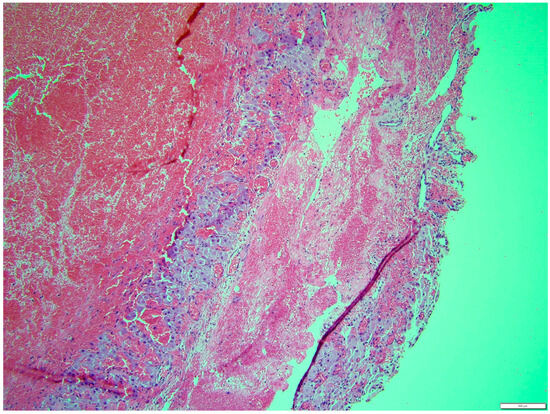

Histologically, both tumor areas were distinctly different from each other (Figure 7 and Figure 8). In the obtained sample for histological examination, the portion of the thecoma was significantly lower (Figure 9). Marked hemorrhage (but not blood-filled lacunae) and very sparse granulation-type connective tissue were observed at the border between both tumor tissues (Figure 10). Hemorrhagic blood masses infiltrated a larger part of the thecoma tissues. A single cystic structure lined with columnar epithelium was found in the hemorrhagic zone, with a very sparse amount of mucus-like material in the lumen (Figure 11).

Figure 7. Distinction between fibroma and thecoma parts. HE, 100× magnification.

Animals 14 01307 g007